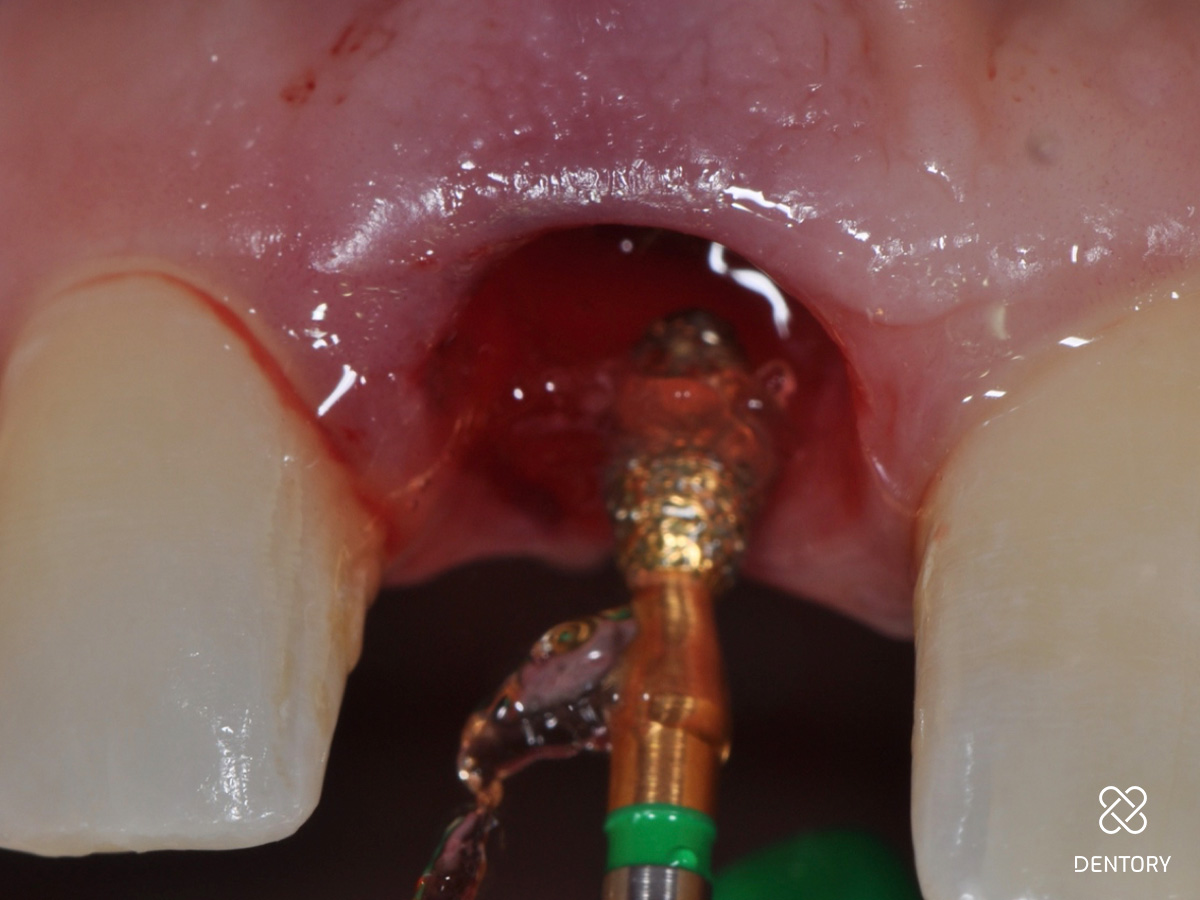

Abbildung 1

Ausgangssituation: Frontalansicht.